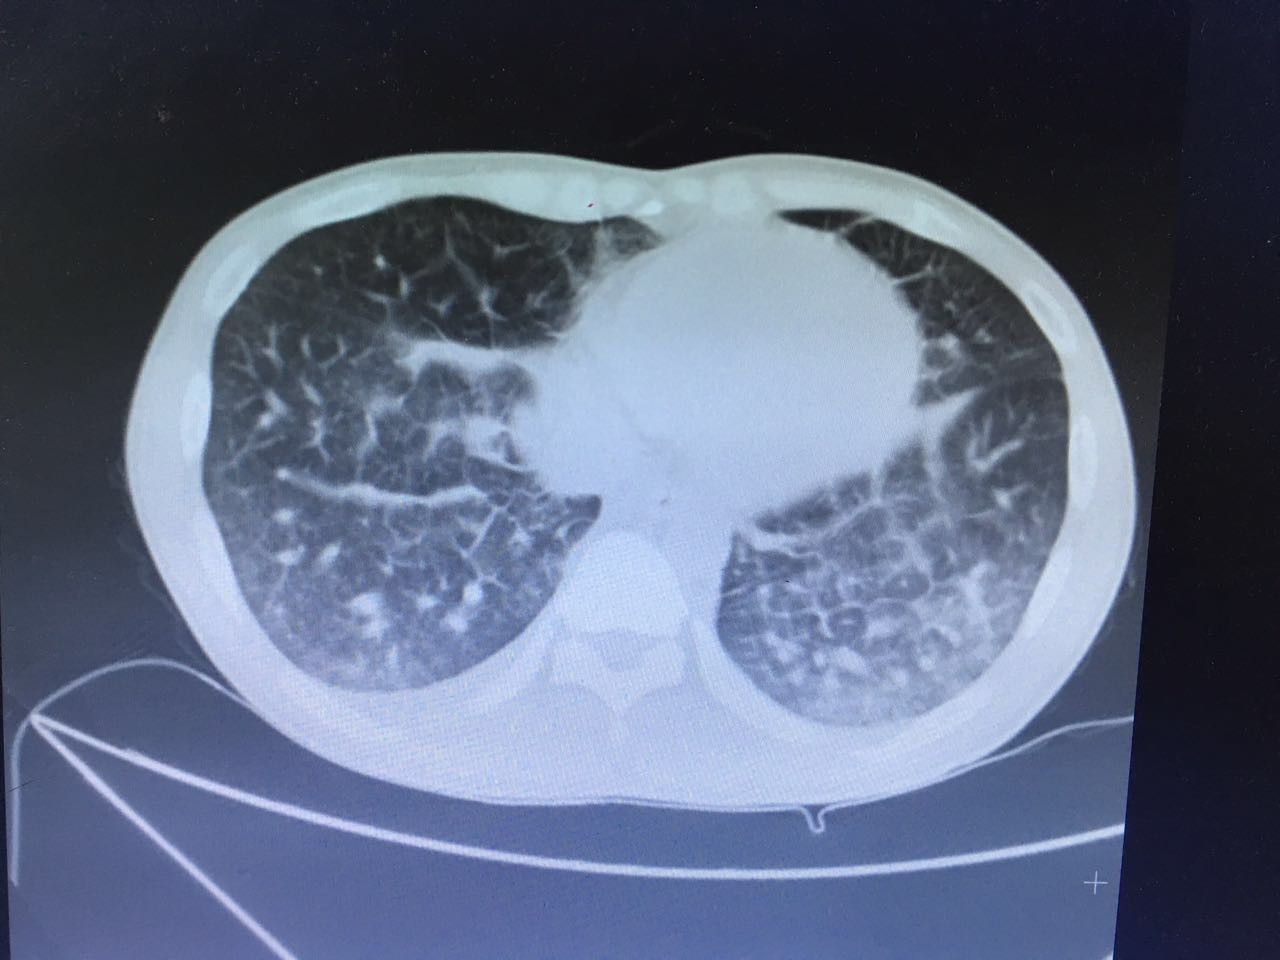

第二天,肺部CT做下来,我们傻了,和胸片差别太大了!从中下肺开始,那是大片的阴影啊!CT提示为间质性肺炎,找放射科主任读片,认为不符合肺结核、肺癌的表现(图1-3.)马上再回到病床前再次确认——没有吸烟史、没有慢性咳嗽史、没有咯血、没有盗汗史。再查体:浅表淋巴结确实不肿大,双肺呼吸音可以算略粗糙也可以算清晰。——这么这么静默的肺部体征,这么这么差的影像学结果,马上补查肿瘤标志物和自身免疫全套吧!

图3